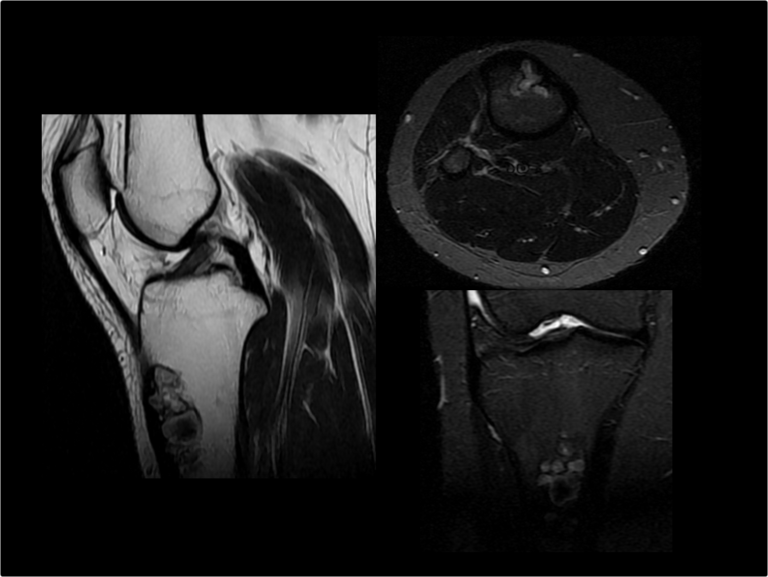

Lesiones meniscales | Repaso anatómico y clasificación de las lesiones

Cuando hablamos de meniscos de la rodilla, estamos hablando de una estructura cuyas lesiones son responsables de un alto porcentaje de los estudios de rodilla que se piden en la práctica cotidiana. Ya sea porque se sospecha una lesión, porque han sido intervenidos quirúrgicamente o porque acompañan la lesión de otras estructuras, las lesiones meniscales…